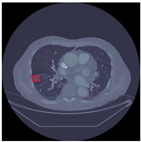

Table 12 demonstrates the results obtained from AlexNet with the SGD optimizer on the Luna16 dataset. The original image was benign, and the CNN architecture AlexNet with the SGD optimizer detected the image as benign. Next, the image was benign and AlexNet with the SGD detected the image as malignant, which was wrongly predict by AlexNet. The next image was malignant, and AlexNet with the SGD optimizer detected it as benign. Finally, the actual image was malignant, and AlexNet with the SGD optimizer detected it as malignant.

Table 12.

Detection results of AlexNet with the SGD optimizer on the LUNA16 dataset.